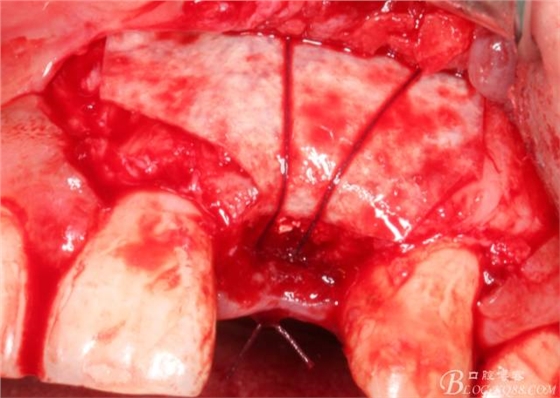

于是我果斷告知患者,手術(shù)失敗了,不能拖延,如不及時處理,炎癥繼續(xù)發(fā)展會很快波及鄰牙牙槽骨。患者接受我的建議。切開翻瓣,骨粉及生物膜消失了,骨吸收嚴(yán)重,幸運的是,因為處理及時,鄰牙骨支持依然存在。

徹底掻刮。